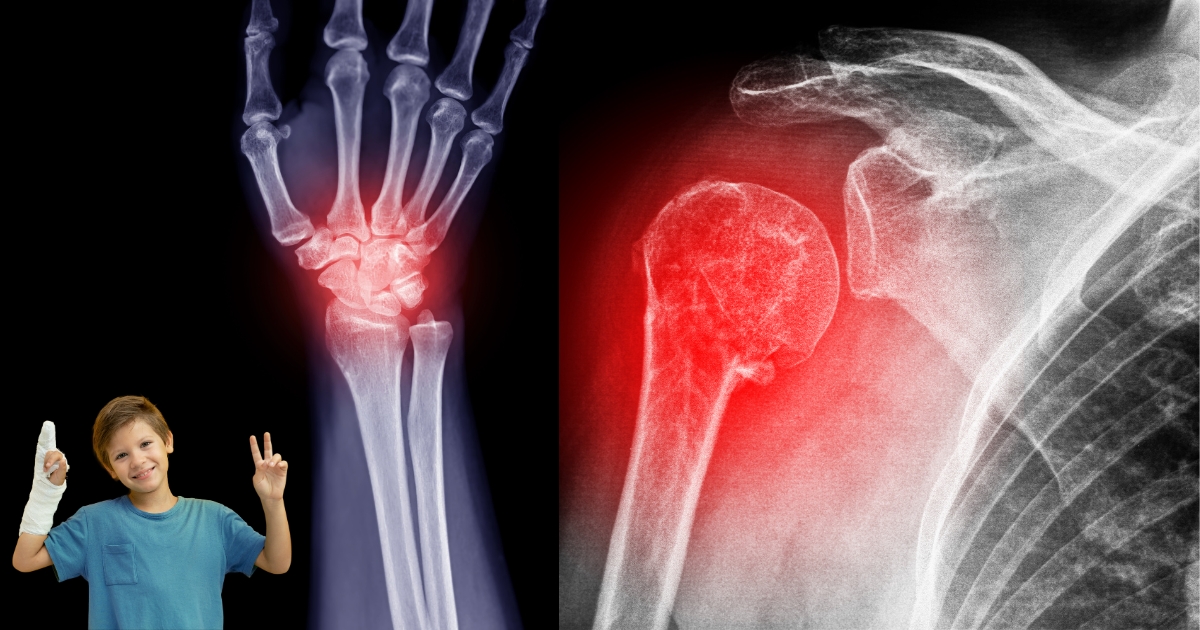

Fractures in the wrist and shoulder can significantly impact your daily life, limiting movement and causing pain. At Orthocenter, we specialize in providing advanced wrist and shoulder fracture treatment in Lahore, ensuring a smooth recovery and restoring mobility. Our expert orthopedic surgeons use state-of-the-art techniques for precise diagnosis and effective treatment plans tailored to each patient.

Effective Wrist & Shoulder Fracture Treatment in Lahore begins with a proper understanding of these injuries. Fractures in these areas can cause severe pain and restricted movement, requiring timely medical intervention.

A wrist fracture occurs when one or more bones in the wrist break due to trauma, falls, or accidents. Common types of wrist fractures include:

A shoulder fracture involves a break in any of the three bones in the shoulder:

- X-rays & CT Scans to determine the type and severity of the fracture